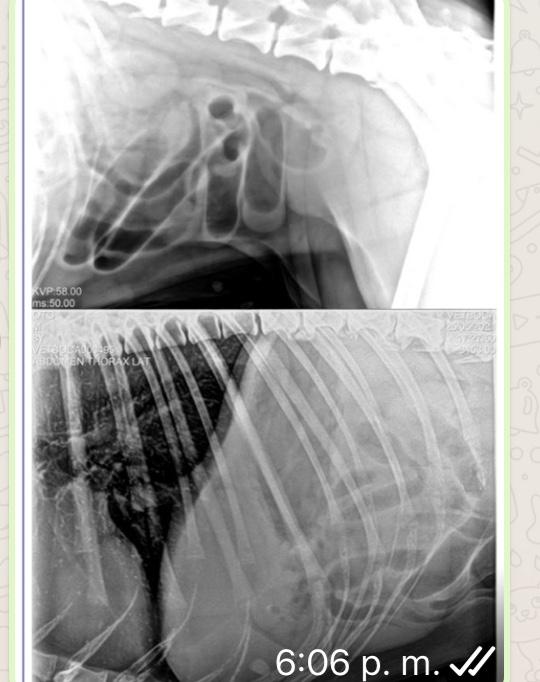

Mí perra luego se ser operada del intestino delgado, cuerpo extraño, comenzó hacer sus heces normal, pero luego de varios días comenzó , primero con vomitó, y ahora su popo es con sangre oscura... podrá ser que su operación comenzó a sangrar nuevamente ?